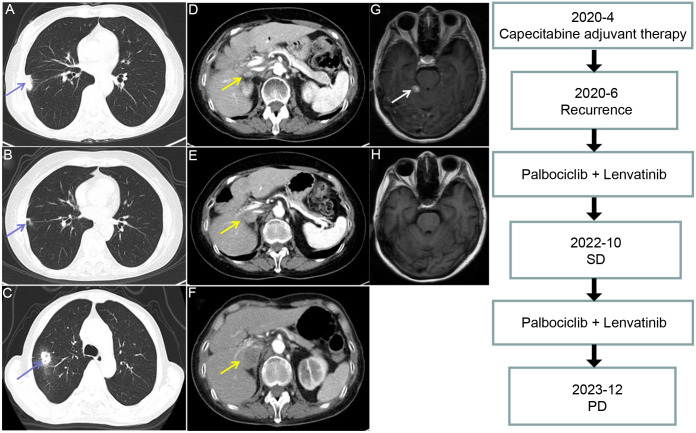

Cyclin-dependent kinase inhibitor 2A/2B (CDKN2A/2B) deletions are frequently identified in patients with biliary tract cancer; however, standard treatment options for this genetic alteration are lacking. Here, we present the case of a 64-year-old woman diagnosed with intrahepatic cholangiocarcinoma and hilar lymph node metastasis who underwent radical surgery. Postoperative pathology confirmed moderately differentiated adenocarcinoma. The tumor recurred during the second cycle of adjuvant chemotherapy following surgery, and the metastatic sites included the cranial region, right lung, and right adrenal gland. Genetic analysis revealed a CDKN2A/2B deletion, indicating palbociclib sensitivity. Subsequently, the patient received palbociclib plus lenvatinib as systemic therapy, along with stereotactic radiotherapy for the intracranial lesion. Notably, the right pulmonary metastasis significantly regressed after 12 months of treatment, with the complete disappearance of the intracranial tumor. However, the disease progressed at 32.2 months, with significant enlargement of the right adrenal gland metastasis and new metastasis in the right lung. The progression-free survival and overall survival were 32.2 months and 34.4 months, respectively. In conclusion, our case demonstrates that palbociclib plus lenvatinib is a promising chemotherapy-free second-line treatment for intrahepatic cholangiocarcinoma with a CDKN2A/2B deletion.